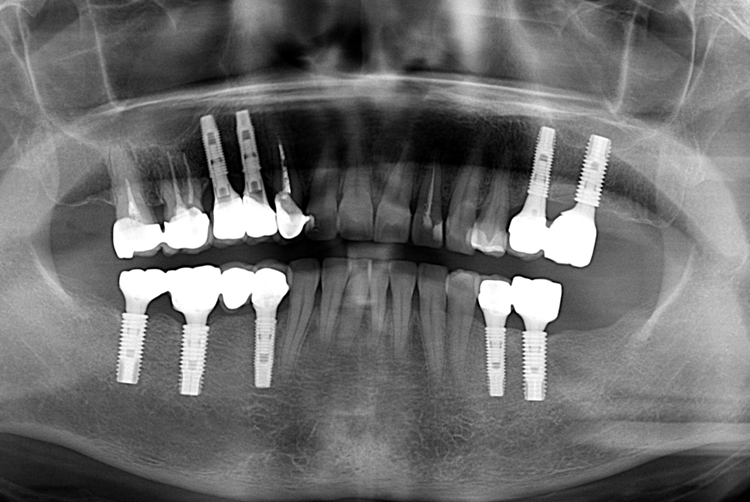

[임플란트] 어금니 임플란트

치료후 : 2018-12-12

세종치과는 많은 환자와 다양한 케이스를 바탕으로

항상 편안한 임플란트 수술을 제공하고자 노력하고,

오래동안 튼튼히 쓸 수 있는 임플란트 수술을 가장 큰 목표로 삼고 있습니다.